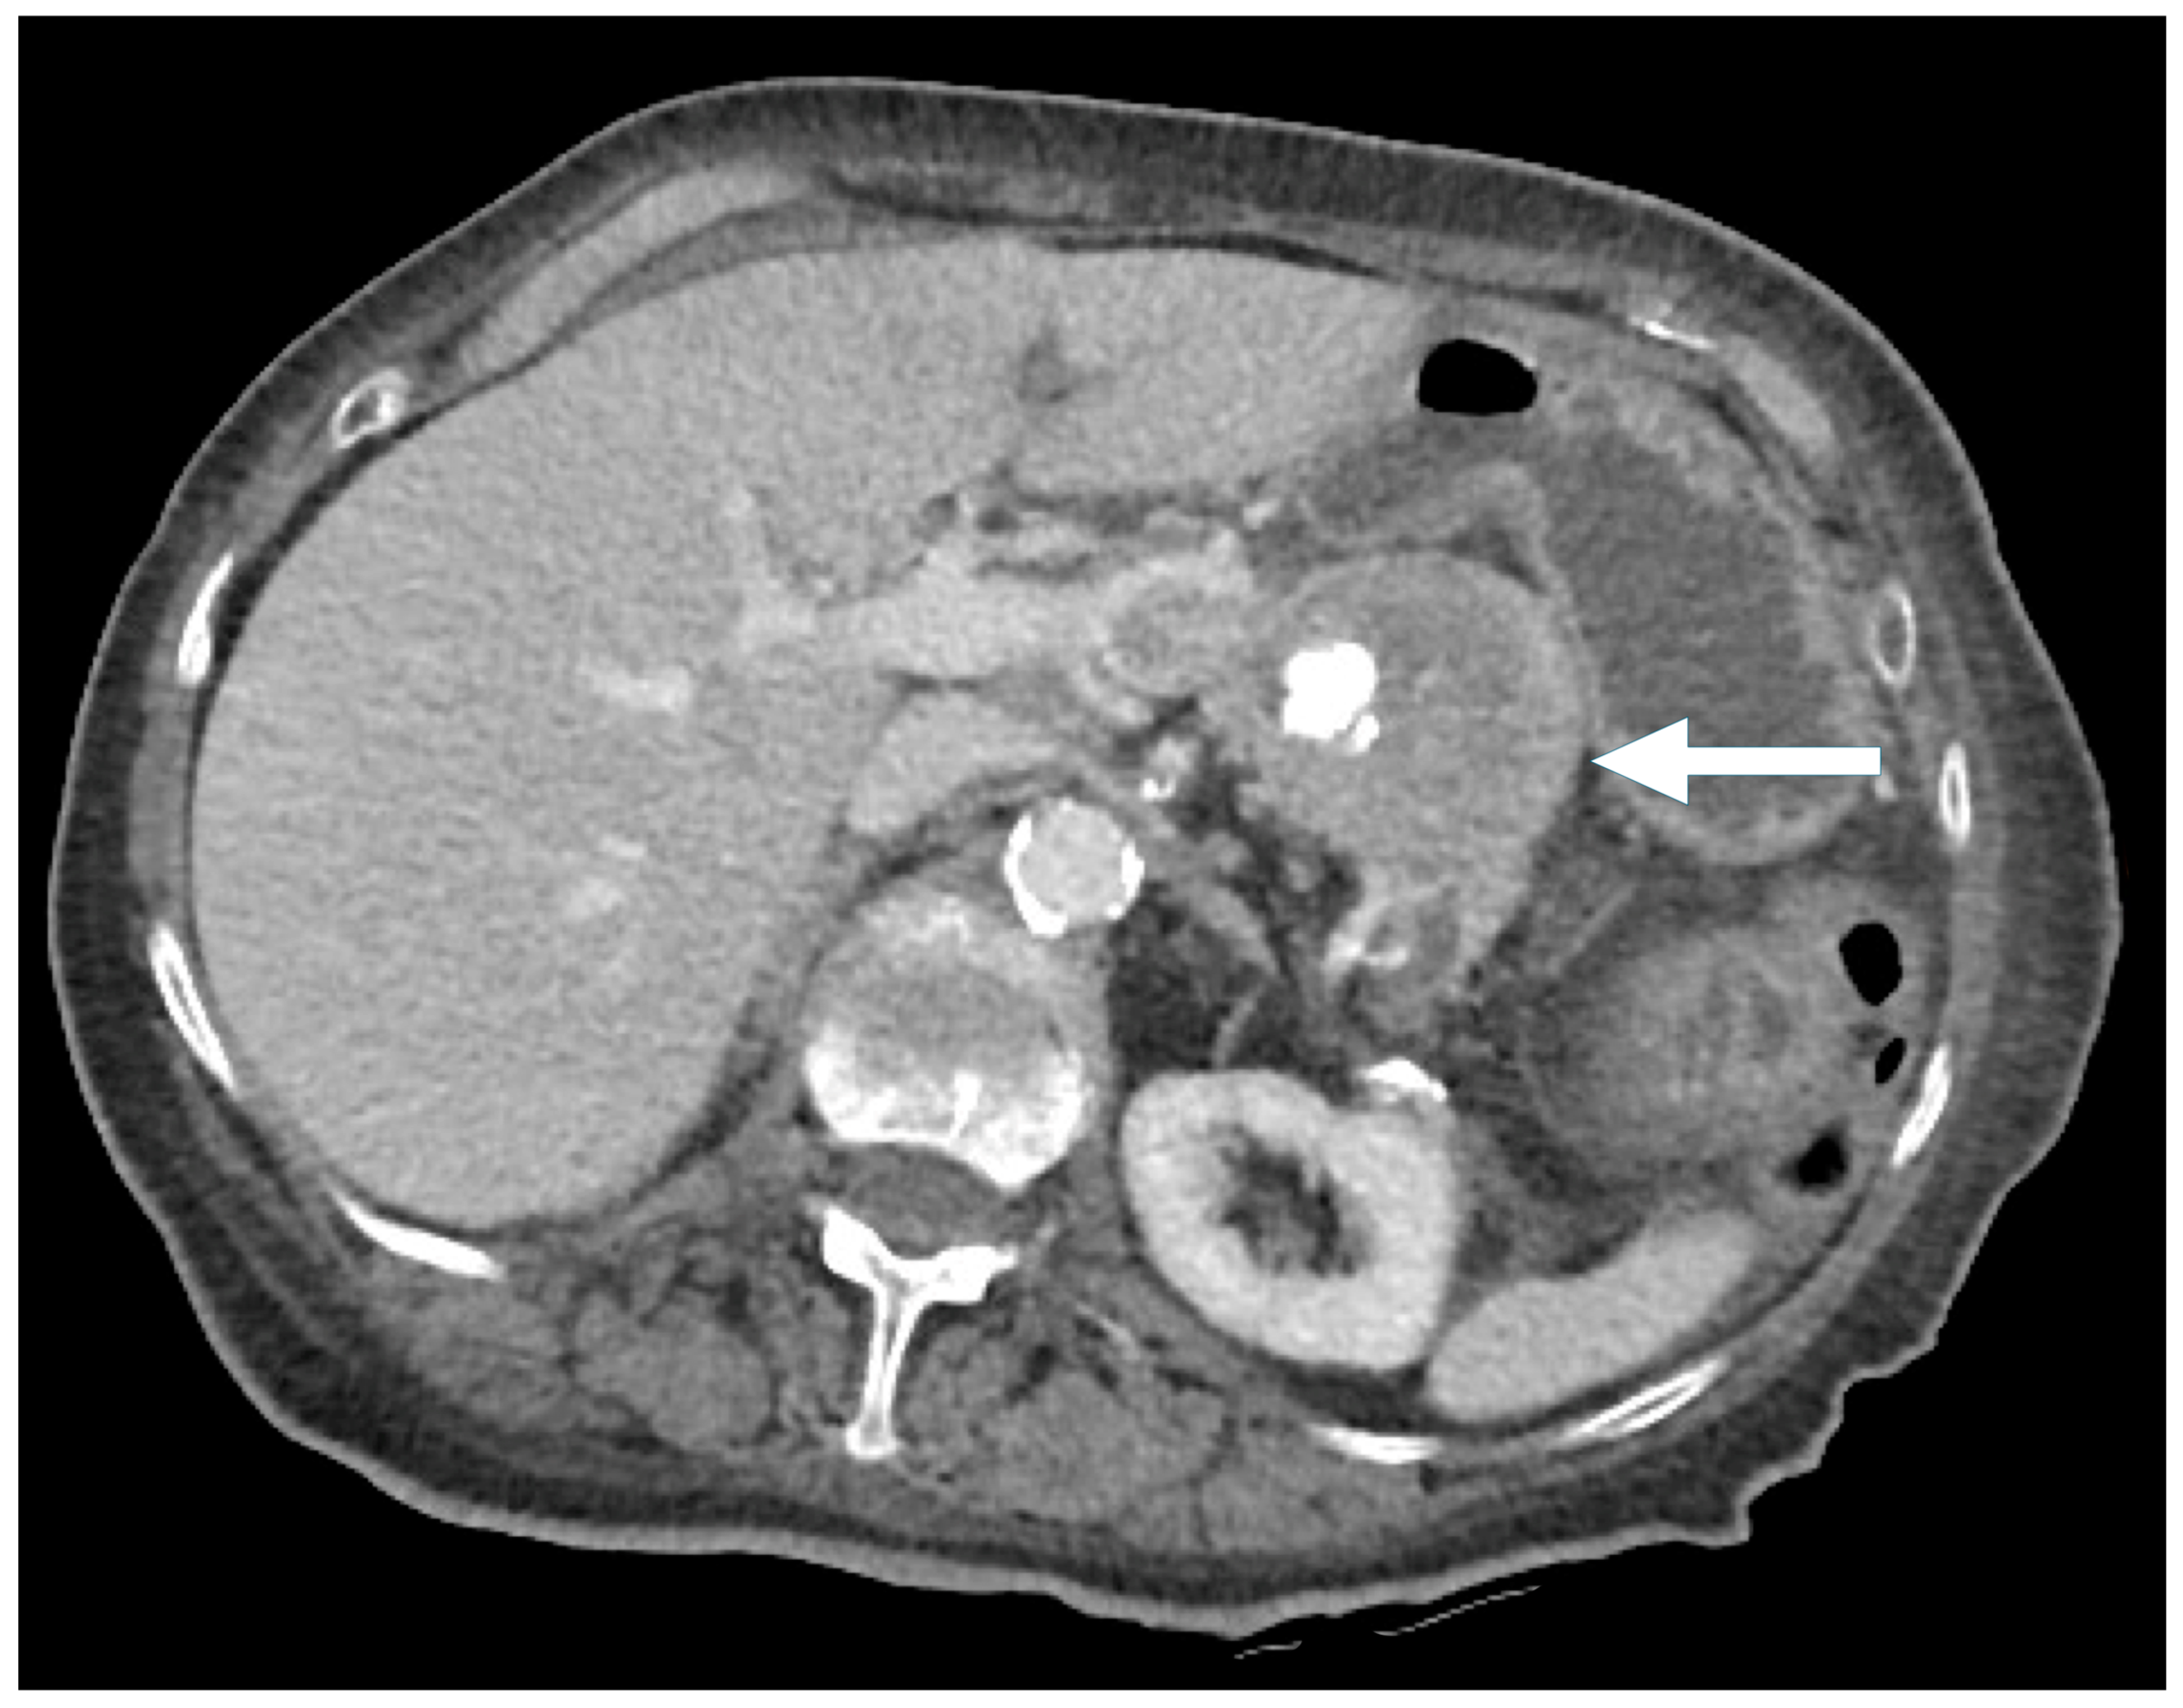

A total of 77 PNEN cases were identified over the study period, of which 39 met the inclusion criteria (Table 1). Cross-sectional imaging was available for all included cases, with CT being the initial modality in 90% and MRI in 10%. Additional imaging with 68Ga-DOTATATE PET or FDG-PET was performed in 82% of cases. Typical PNENs accounted for 54% of the cohort and were characterized by well-defined, hypervascular solid lesions (Figure 1, Figure 2 and Figure 3). In contrast, atypical PNENs comprised 46% (n = 18), including 7 cystic lesions (18%) and 11 hypoenhancing lesions (28%).

Figure 4. A 56-year-old man presenting with painless jaundice. Contrast-enhanced CT demonstrates a pancreatic head mass (arrow) with mixed solid and cystic/necrotic components, showing arterial phase hyperenhancement. (left) Axial arterial phase CT. (right) Coronal arterial phase CT.

Symptomatic presentation was more frequent in the cystic PNENs (57% vs. 29% in the typical PNENs) (Figure 4 and Figure 5), and the lesions were larger (median size 2.5 cm vs. 1.7 cm). Calcifications and duct dilatation were also more common in the cystic PNENs (29% vs. 15% for calcifications and 14% vs. 10% for duct dilatation). Importantly, none of the cystic PNEN cases demonstrated locoregional invasion or metastatic disease.